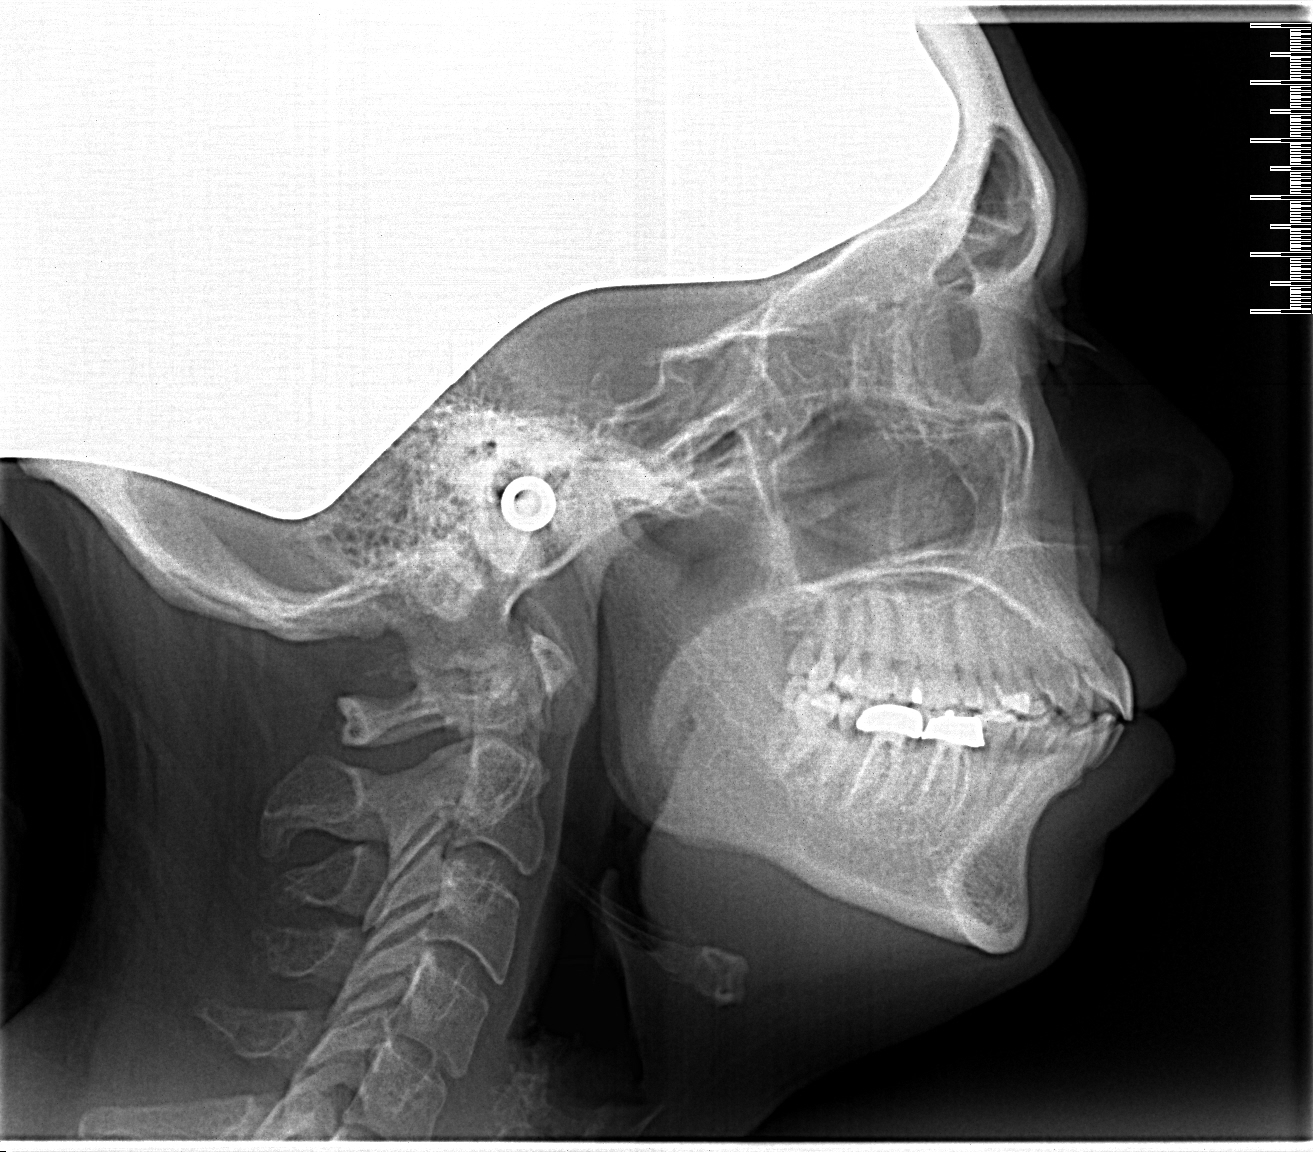

Al enige tijd ben ik (44) aan een beugel aan het denken en nu eindelijk de foto's gemaakt.

Mijn angst is dat het gebied rondom mijn kronen heel erg gevoelig wordt. ik merk nu ook al dat de kronen kwetsbaarder zijn dan de rest van mijn tanden (soms steken).

Nu denk ik dat er best wel wat druk op deze kronen komt te liggen. Ze liggen immers naast elkaar en de kiesjes naast de snijtand worden allevier getrokken om ruimte te maken. (Mijn voor- en ondertanden moeten dus naar achter).